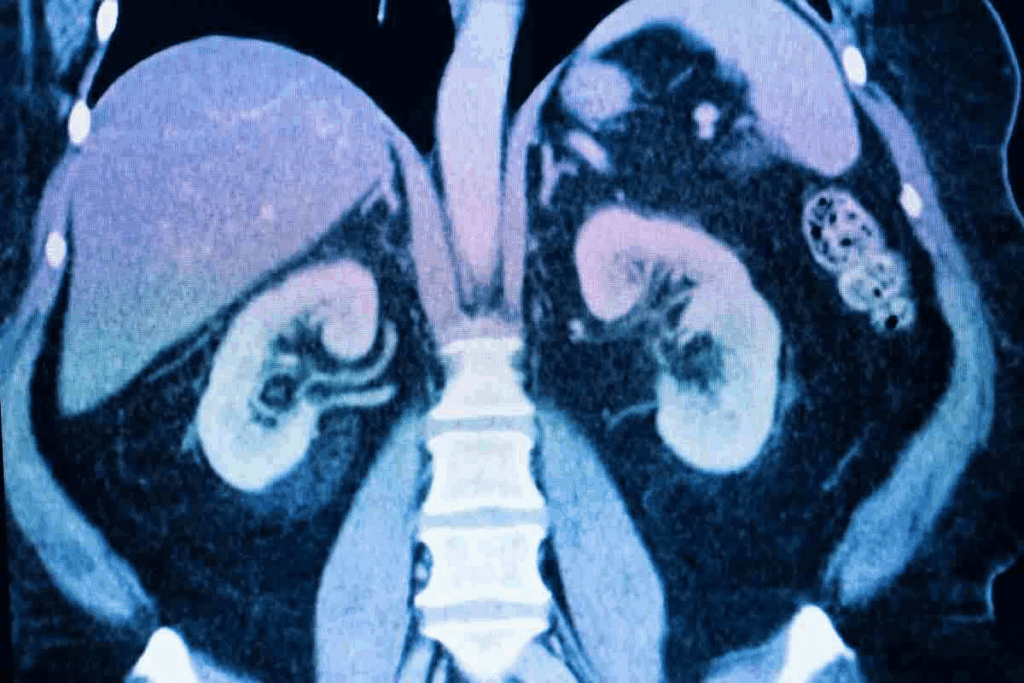

When preparing for a CT scan of your abdomen or pelvis, your doctor may ask you to consume a CAT scan drink liquid before the procedure. This oral contrast is essential for helping radiologists obtain clear and detailed images, ensuring an accurate diagnosis.

The CAT scan drink liquid is swallowed prior to the scan to help differentiate the digestive tract from surrounding organs and tissues. This improves the accuracy of the images, allowing our medical team to provide a precise diagnosis and an effective treatment plan tailored to your needs.

Oral contrast plays a crucial role in CT imaging by enhancing the visibility of the digestive tract. When preparing for a CT scan, patients are often required to consume a contrast drink that contains specific agents to highlight the gastrointestinal system. This contrast agent is crucial for diagnostic accuracy, as it allows radiologists to distinguish between various structures within the abdominal cavity.

One of the key challenges in abdominal CT imaging is distinguishing the digestive tract from adjacent structures. Oral contrast helps address this issue by providing a clear contrast between the lumen of the bowel and the surrounding tissues. This is particularly important when diagnosing conditions that affect the gastrointestinal system.